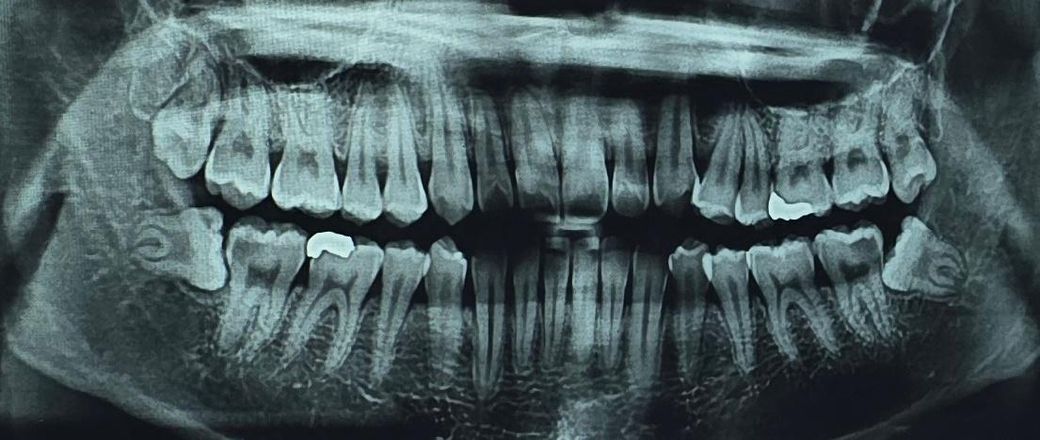

신경치료 후 사랑니 발치 질문 (어려운 사랑니인가요??)

아래 양 쪽 모두 한쪽은 신경치료, 한쪽은 충치치료를 먼저 받고 사랑니 발치를 하자고 하셨는데, 발치할 때 신경치료한 부분에 문제는 없겠죠..??

그리고 누워있는 매복 사랑니는 뺄 때 힘들다고 하는데, 통증이 심하다거나 빼는 과정이 어려운 사랑니인지 궁금합니다..! 20대 초반이고 겁쟁이라서 질문드려요..감사합니다

사랑니가 기울어져 나있고 뿌리가 휘어져 있어. 발치를 하는 과정이 힘들 수도 있습니다. 하지만 20대라면 뼈가 단단한 편이 아니기 때문에 사랑니가 나오는데 수월할 수 있습니다. 사랑니를 발치하고 신경치료를 하는 치료는 어려운 치료는 아닙니다.

신경과 가깝고 옆 어금니와 겹쳐 있어서 주의할 필요는 있으나 다행히 뿌리가 안쪽으로 수렴하는 형태이고, 아직 20대라 젊어서 아주 어려운 케이스는 아닐 것 같습니다. 발치 시 마취만 잘되면 통증 없습니다.

사랑니는 누워있는 각도가 큰 편이라 난이도 또한 높은 편입니다. 구강외과 전문의한테 뽑는 게 좋아보입니다.